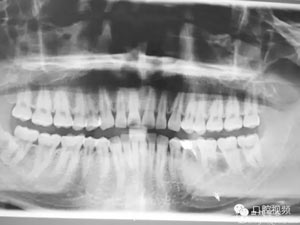

圖1.術(shù)前的全景片影像檢查,35移位至36、37之間。

患者、盧xx、男、19歲。主訴:左側(cè)下頜乳磨牙未脫落,要求檢查。??茩z查:左側(cè)下頜第二乳磨牙有充填物。無松動,全景片檢查。35移位至36、37之間。頰舌側(cè)均不能觸及隆起。CBCT檢查:35位于36、37的舌側(cè)。表面骨質(zhì)約2mm左右。35完全骨埋伏,36的遠(yuǎn)中牙根疑是吸收。建議35暫觀察。置留不取?;颊咭蟀纬龘?dān)心壓迫36牙根或者發(fā)生囊性變。術(shù)前簽手術(shù)同意書。